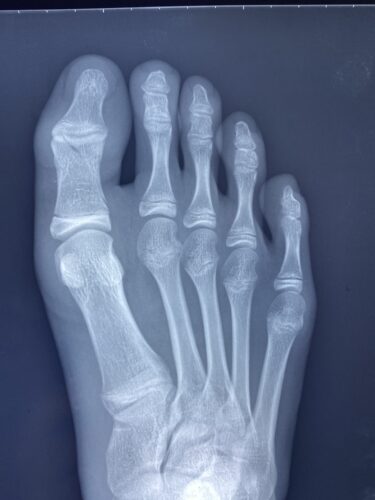

第5中足骨骨折の1症例について